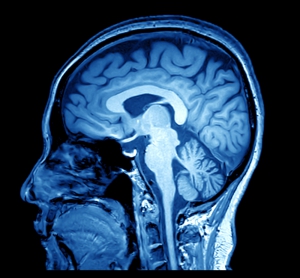

Neuroradiologists use a wide range of techniques including MRI, CT, carotid/cerebral angiogram, discogram, lumbar puncture, myelogram, and fluoroscopy.

Specialists in Neuroradiology at ARS also provide advanced imaging techniques including perfusion, spectroscopy, diffusion tensor imaging, and functional MRI to diagnose and characterize neurologic conditions.